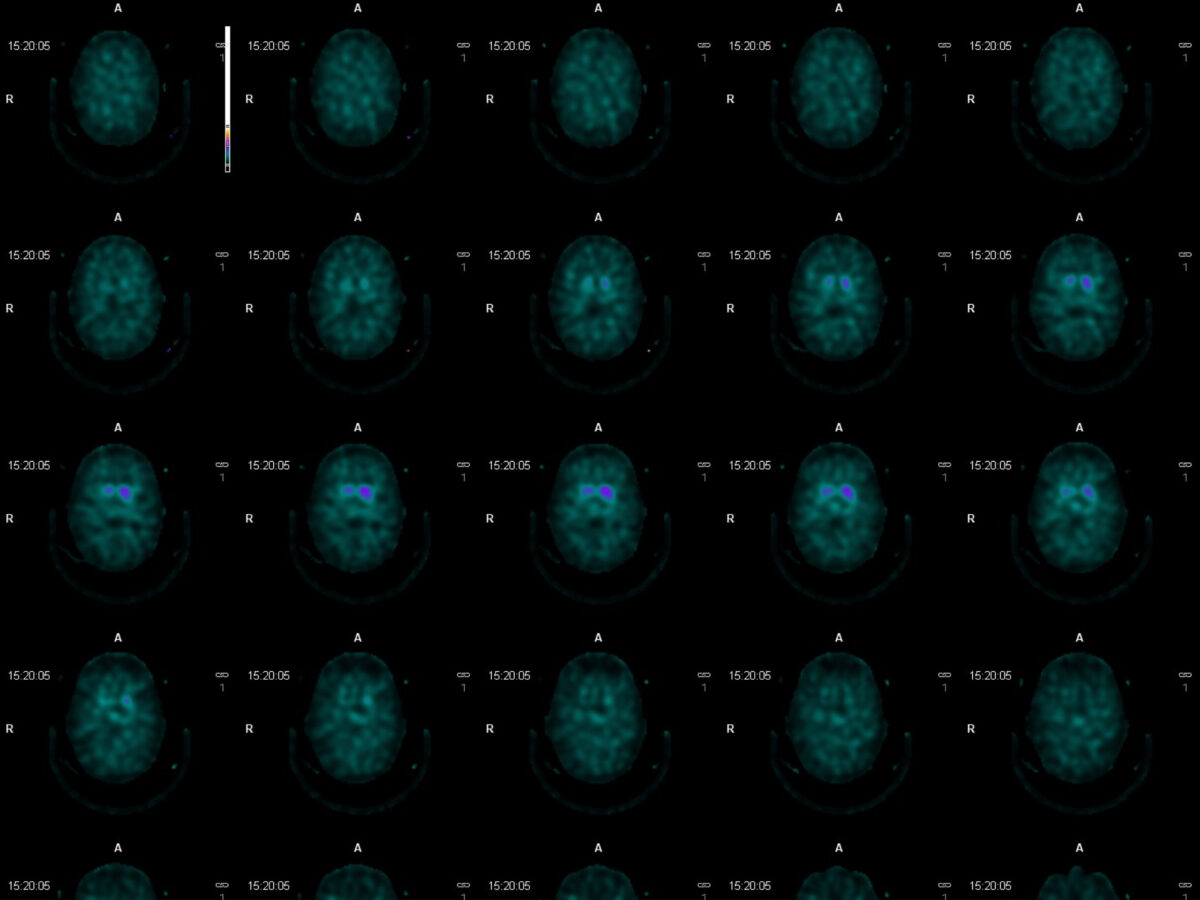

Radioaktives Iod-123 fliesst langsam durch meinen Körper. Trotz Jod-Tabletten schmerzt der Kiefer. Während einiger Stunden liege ich im Hörnli. Das